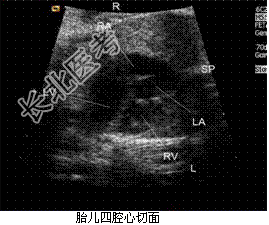

- [材料题] 孕妇,27岁,孕1产0孕25周2d,实验室检查无明显异常。胎儿心脏超声:下腔静脉与形态学右心房连接,肺静脉与形态学左心房连接,其他表现见下图。

(L-左侧,R-右侧,LA-左心房,RA-右心房,LV-左心室,RV-右心室,AAO-升主动脉,MPA-主肺动脉,SP-脊柱)。

- 简答题1、根据上述声像图,该胎儿先天性心脏病最可能为什么?